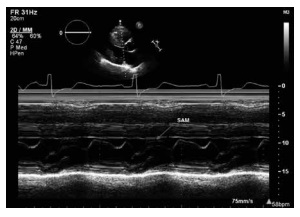

Um paciente de 41 anos de idade, hipertenso,

em uso de losartana, com queixa de dispneia durante os

esforços e desconforto precordial inespecífico nas últimas

semanas. Seguem imagens do ecocardiograma a seguir.

Com base nessa situação hipotética e nas imagens acima, assinale a alternativa que apresenta a etiologia adequada do quadro.